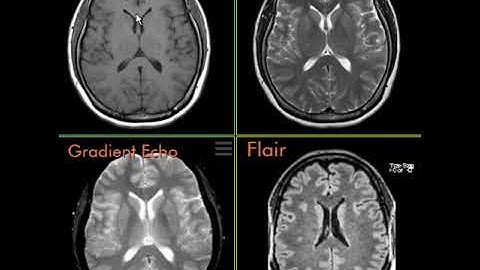

SEQUENCE GRADIENT ECHO PADA ALAT MRI